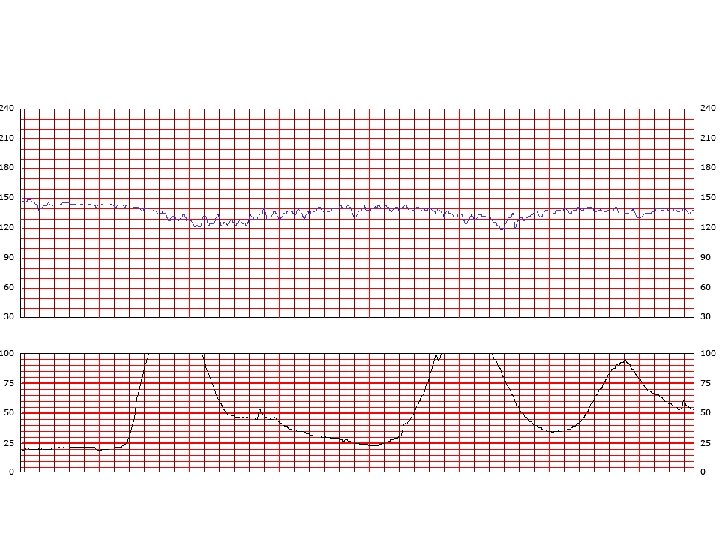

Interpretation of the Fetal Heart Tracing The interpretation of the fetal heart rate tracing should follow a systematic approach with a full qualitative and quantitative description of the following: • Baseline FHR rate variability • Periodic changes accelerations decelerations • Frequency and intensity of uterine contractions

Baseline Fetal Heart Rate The baseline FHR is the heart rate during a 10 minute segment rounded to the nearest 5 beat per minute increment excluding periods of marked FHR variability, periodic or episodic changes, and segments of baseline that differ by more than 25 beats per minute. • The minimum baseline duration must be at least 2 minutes. • If minimum baseline duration is < 2 minutes then the baseline is indeterminate. • Normal baseline = 110 -160 bpm

Baseline variability The minor fluctuations in baseline FHR occuring at three to five cycles per minute. It is measured by estimating the difference in beats per minute between the highest peak and lowest trough of fluctuation in a one-minute segment of the trace.

FHR Variability Absent variability = Amplitude range undetectable Minimal = < 5 BPM Moderate = 6 to 25 BPM Marked = > 25 BPM